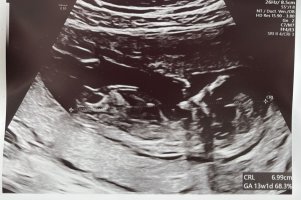

Fikk ta screenshot fra videoen, babyen var så aktiv så var vanskelig å få tydelige bilderVar 12+5 her. Noen som klarer å tyde, gutt eller jente?